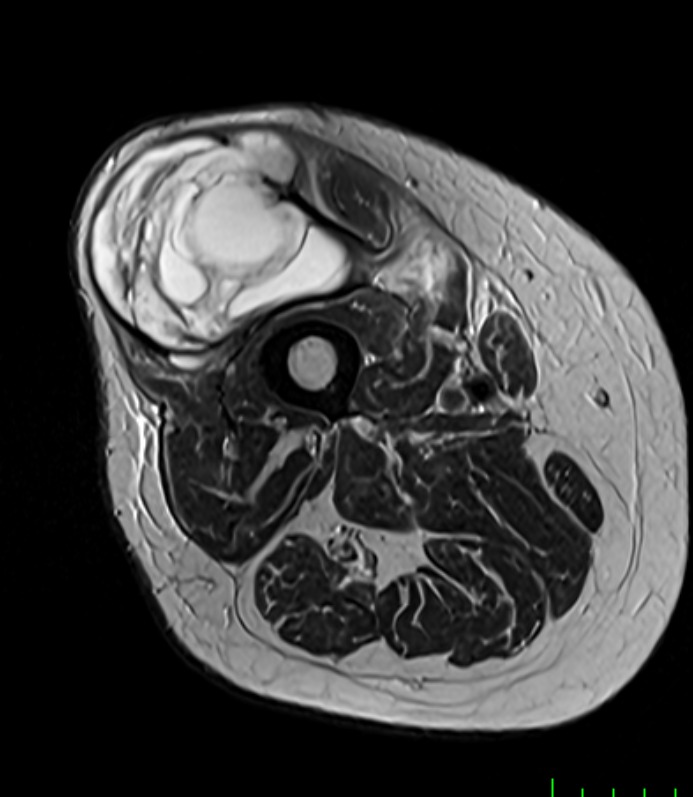

Muscle Cancer

Healthy Eye